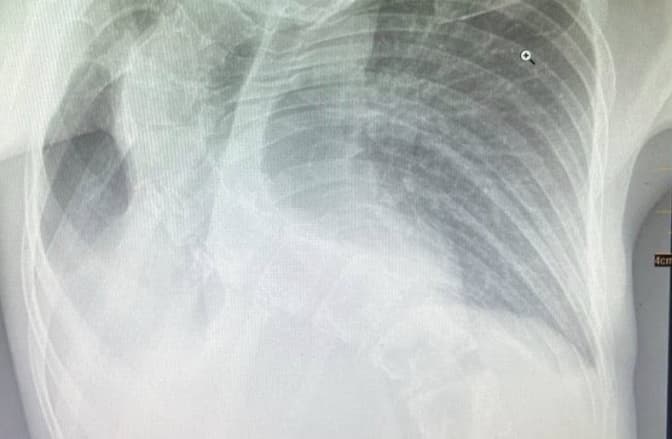

Covid-19 – Головне. Від запалення легень у Городоцькій районній лікарні померла 11-річна дівчинка. Каретою швидкої медичної допомоги дитину уже везли із лікарні, що в Судовій Вишні до львівського ОХМАТДИТу, але її стан різко погіршився, то ж прийняли рішення вести у Городоцьку лікарню, де дівчинка й померла .Що саме стало причиною такого різкого погіршення стану, наразі не відомо. За словами керівниці Львівської обласної дитячої лікарні «ОХМАТДИТ» Бурди, вони лише знають, що дитина хворіла три дні.